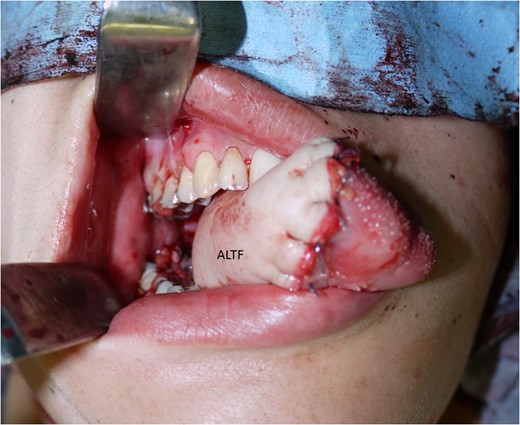

The surgical treatment for this patient involved tracheostomy, hemi-glossectomy and right-sided selective neck dissection when the patient was in her 28th week of pregnancy. Throughout the surgery, the patient was given a continuous intravenous infusion of ritodrine hydrochloride (100 mg in 500 ml) in order to provide tocolysis and prevent premature labour. A tracheotomy was preformed and the patient underwent a modified rapid sequence induction using fentanyl, thiopentone and rocuronium bromide. Anaesthesia was maintained with sevoflurane. A continuous fentanyl infusion provided analgesia and paralysis was maintained with boluses of atracurium besylate. Obstetricians were standing by for unexpected delivery. A cardiotocograph was used to monitor the foetus. The tissue defect was reconstructed with an antero-lateral thigh flap (Figs 3–5). The descending branch of lateral circumflex femoral artery was anastomosed to her right facial artery. One comitant vein was anastomosed to her external jugular vein in end-to-end fashion with a 2.5 mm microvascular anastomotic device. The other comitant vein was anastomosed in the same way to a branch of internal jugular vein with a 2.0 mm coupler. Heparin-saline solution (5000 units in 100 ml) was used to irrigate the anastomotic sites. Systemic heparin administration was not done during the operation. Lidocaine (2%) was used as vasodilator. Prostaglandin E1 was not administered. The operation took 7 h and 40 min. Blood loss was estimated to be 340 ml and no blood transfusion was required. Throughout the operation, no remarkable incidents were noted on the electronic foetal monitoring.

A free antero-lateral thigh flap was harvested from her right thigh.

The antero-lateral thigh flap (ALTF) was transferred to her neck area. The descending branch of lateral circumflex femoral artery (blue arrows indicating) was anastomosed her right facial artery. A comitant vein was anastomosed to her external jugular vein in end-to-end fashion with a 2.5 mm microvascular anastomotic device (yellow arrow). The other comitant vein was anastomosed in the same way to a branch of internal jugular vein (white arrow).

The antero-lateral thigh flap (ALTF) was pulled through, trimmed and sutured to fill the tongue defect.